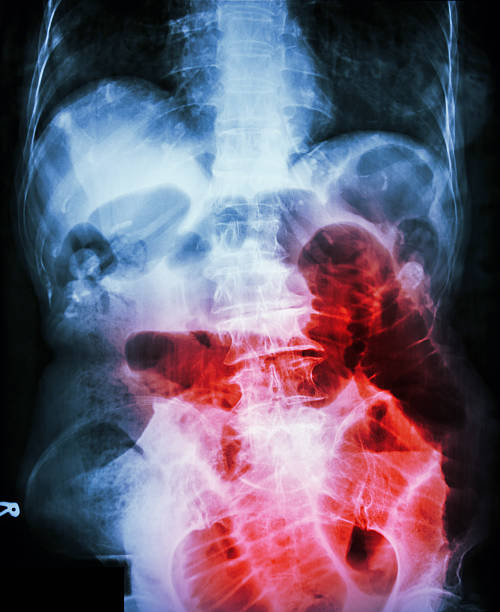

장폐색으로 인한 변비는 대장 내부에서 대변이 막혀서 대변을 배출하기 어려운 상황을 말합니다. 대변이 막혀 있어서 배출이 어렵고, 배출하려고 노력하면 통증이나 출혈 등의 증상이 나타날 수 있습니다. 대장 내부에서 대변이 막히는 원인으로는 대장암, 섬유화, 협착, 분절증 등이 있을 수 있습니다.

일부 장폐색 환자는 변비 대신 설사 증상을 나타낼 수도 있습니다. 이 경우에는 대장이 막히면서 위장관의 상위부분에서 발생한 설사로 인한 것입니다. 설사 증상은 대장 내부에서 배출되지 못한 대변이 있을 때, 위장관의 상위부분에서 물이 과다 배출되어 발생하는 경우가 많습니다.